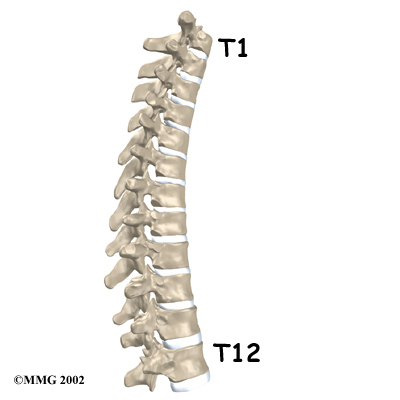

The is made up of the middle 12 vertebrae. Doctors often refer to these vertebrae as T1 to T12. The thoracic spine starts at the base of the neck. The lowest vertebra of the thoracic spine, T12, connects below the bottom of the rib cage to the first vertebra of the lumbar spine, called L1.

The is made up of the middle 12 vertebrae. Doctors often refer to these vertebrae as T1 to T12. The thoracic spine starts at the base of the neck. The lowest vertebra of the thoracic spine, T12, connects below the bottom of the rib cage to the first vertebra of the lumbar spine, called L1.

The upper half of the thoracic spine is much less mobile than the lower section, making disc herniations in the upper thoracic spine rare. About 75 percent of thoracic disc herniations occur from T8 to T12, with the majority affecting T11 and T12.

The upper half of the thoracic spine is much less mobile than the lower section, making disc herniations in the upper thoracic spine rare. About 75 percent of thoracic disc herniations occur from T8 to T12, with the majority affecting T11 and T12.

The upper half of the thoracic spine is much less mobile than the lower section, making disc herniations in the upper thoracic spine rare. About 75 percent of thoracic disc herniations occur from T8 to T12, with the majority affecting T11 and T12.

The upper half of the thoracic spine is much less mobile than the lower section, making disc herniations in the upper thoracic spine rare. About 75 percent of thoracic disc herniations occur from T8 to T12, with the majority affecting T11 and T12.